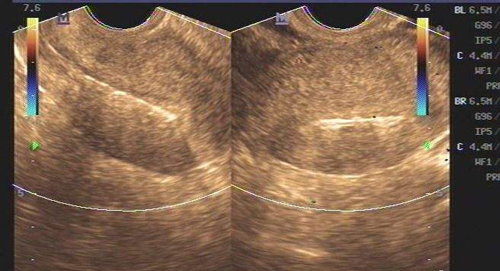

AFC是窦卵泡计数的缩写,是指利用B超彩超等等对卵巢的卵泡数目、大小来进行其的计数手段之一,而窦卵泡常说的是女性卵巢内直径在2-10mm的小卵泡,而通过窦卵泡计数也能够非常好的反应出卵巢储存功能等等。

女性在,最开始进行窦卵泡计数检查的时候,对于什么是窦卵泡计数都会感觉到一定的迷茫,简单的来说窦卵泡就是卵巢中成长出最为原始的3级卵泡,在阴道超声或者彩超的帮助下进行窦卵泡计数,在它们的帮助下,可以最为正确的评估与准确的计数出数量,因为女性的生育能力就是随着时间的改变而改变的,所以在医学上来说,窦卵泡计数是迄今为止最好的办法,能够在任何情况下让人知道卵巢的储存功能,以及在接受试管婴儿手术的时候也要根据这种方法来进行判断卵巢对药物反应,以增加成功率,窦卵泡计数意思就是通过这些办法计算出基础卵泡的个数,从而得到需要的结果。

通过阴超的方式见监测,而不管是哪一种方式,它们最终都是窦卵泡计数监测通常都是用起来起到观察基础卵泡的作用,而对于窦卵泡计数监测的方式非常的多,但是监测的使用方法也是有好有坏的。

在2D阴超检查的时候必须进行进行对膀胱排空后方可进行,而常常需要在两个平面进行连续的扫查,找出成像较佳平面,并进行超声调整后再做最为准确的卵泡液与卵巢间质间的对比度。

3D阴超检查

相对于2D阴超来说3D阴超下过要好一点,3D阴超是同时利用3个垂直平面存储和分析产生体积,通过多平面交叉进行窦卵泡计数检查,将效果发挥到最佳,在较好切面直接进行最佳图像参数和最大采集角,将成像图片质量提升到最高